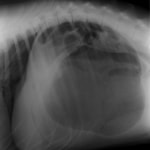

術前のレントゲン